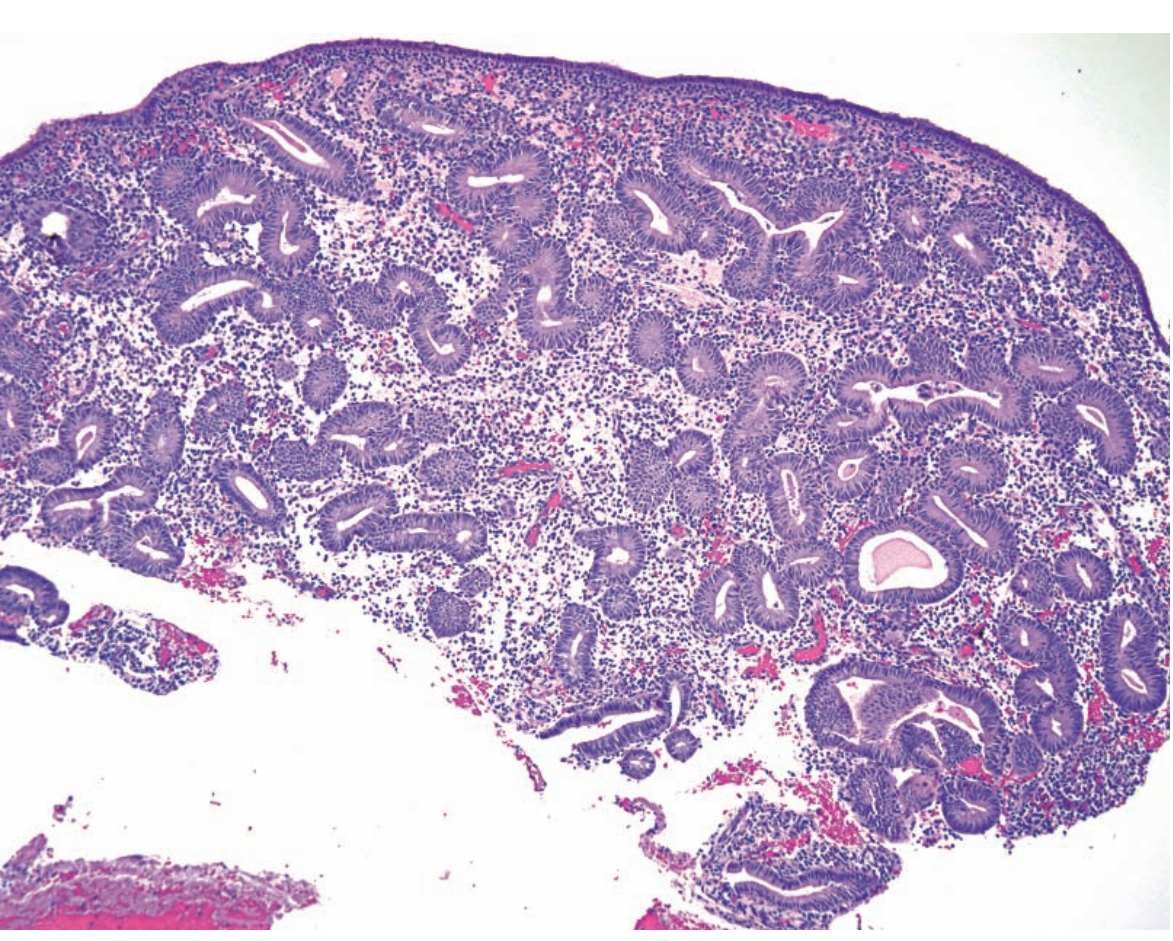

Leiomyoma Arrow/Arrowhead: Parallel and perpendicular bundles Inset: "Corkscrew" nuclei